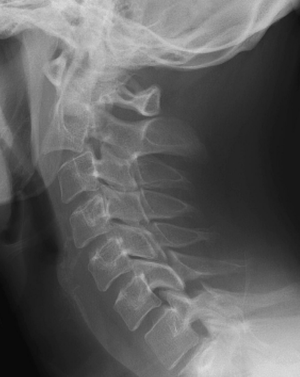

Hangman's fracture

- Bilateral C2 pedicle fracture (leads to C2 displacing anteriorly on C3)

- Xray or CT cervical